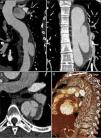

Imagens da angioTC realizada imediatamente após a TEVAR (A, B e C) e da angioTC de controlo seis meses após o tratamento (D, E e F). Observam‐se as duas endopróteses aórticas parcialmente sobrepostas, recobrindo o IMH e o canal arterial, desde a artéria subclávia esquerda até ao início da aorta abdominal, sem evidência de endoleaks (A). Na figura C, a imagem de DAo distalmente à prótese (seta), com origem ao nível do tronco celíaco e estendendo‐se até à artéria mesentérica superior. Comparativamente à angioTC pós‐procedimento, na angioTC de controlo aos seis meses observa‐se uma regressão quase total do IMH (D e E) e o desaparecimento da imagem de DAo abdominal (F).

Após a alta, o doente manteve seguimento regular em consulta externa de cardiologia. Na angioTC de controlo realizada aos seis meses mantinha bom resultado do tratamento e constatou‐se uma regressão quase total do IMH e desaparecimento da imagem de DAo abdominal (figura 4D, E e F). Atualmente, com 18 meses de follow‐up, mantém‐se clinicamente estável, assintomático e com perfil tensional controlado (média das 24 horas de 107/73mmHg em monitorização da pressão arterial em ambulatório), e mantendo bom resultado imagiológico na angioTC dos 12 meses.